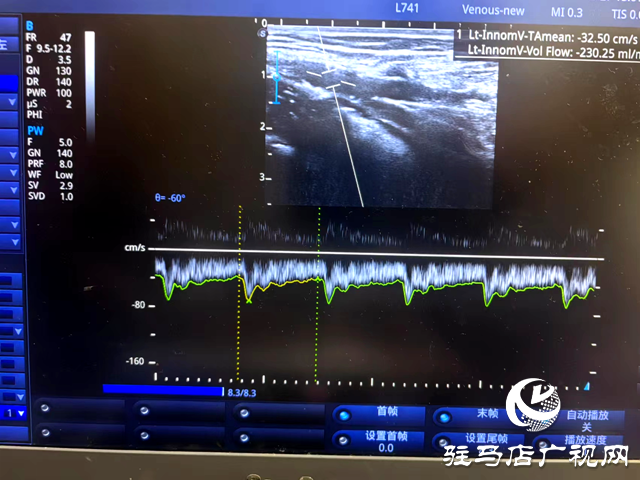

接诊后,邱明生主任进行了详细问诊,随后完善前臂血管彩超。彩超检查显示,付女士患有严重的头静脉狭窄(内膜增生),最窄处内径仅有1.2mm,内瘘血流量230ml/min,远小于血液透析所要求的流量大于500ml/min。得知这一情况,付女士焦急万分又无可奈何,“这该怎么办呢?我已经做过两次扩张了!”

术后,经彩超评估,付女士肱动脉血流量由植入前230ml/min扩容到638ml/min,支架成功打通了狭窄内瘘,建立起透析“生命线”通路。术后即开始了正常的血液透析治疗。